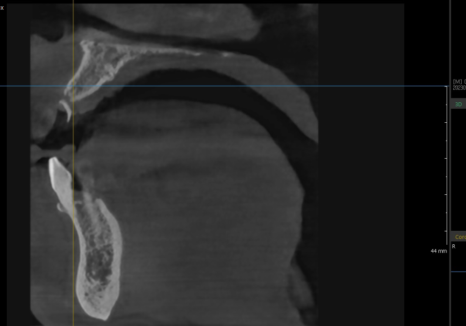

다행히 CT 분석 결과,

잇몸뼈의 폭과 길이가 충분하셔서

발치 당일 즉시 임플란트를

식립할 수 있었습니다.

240119